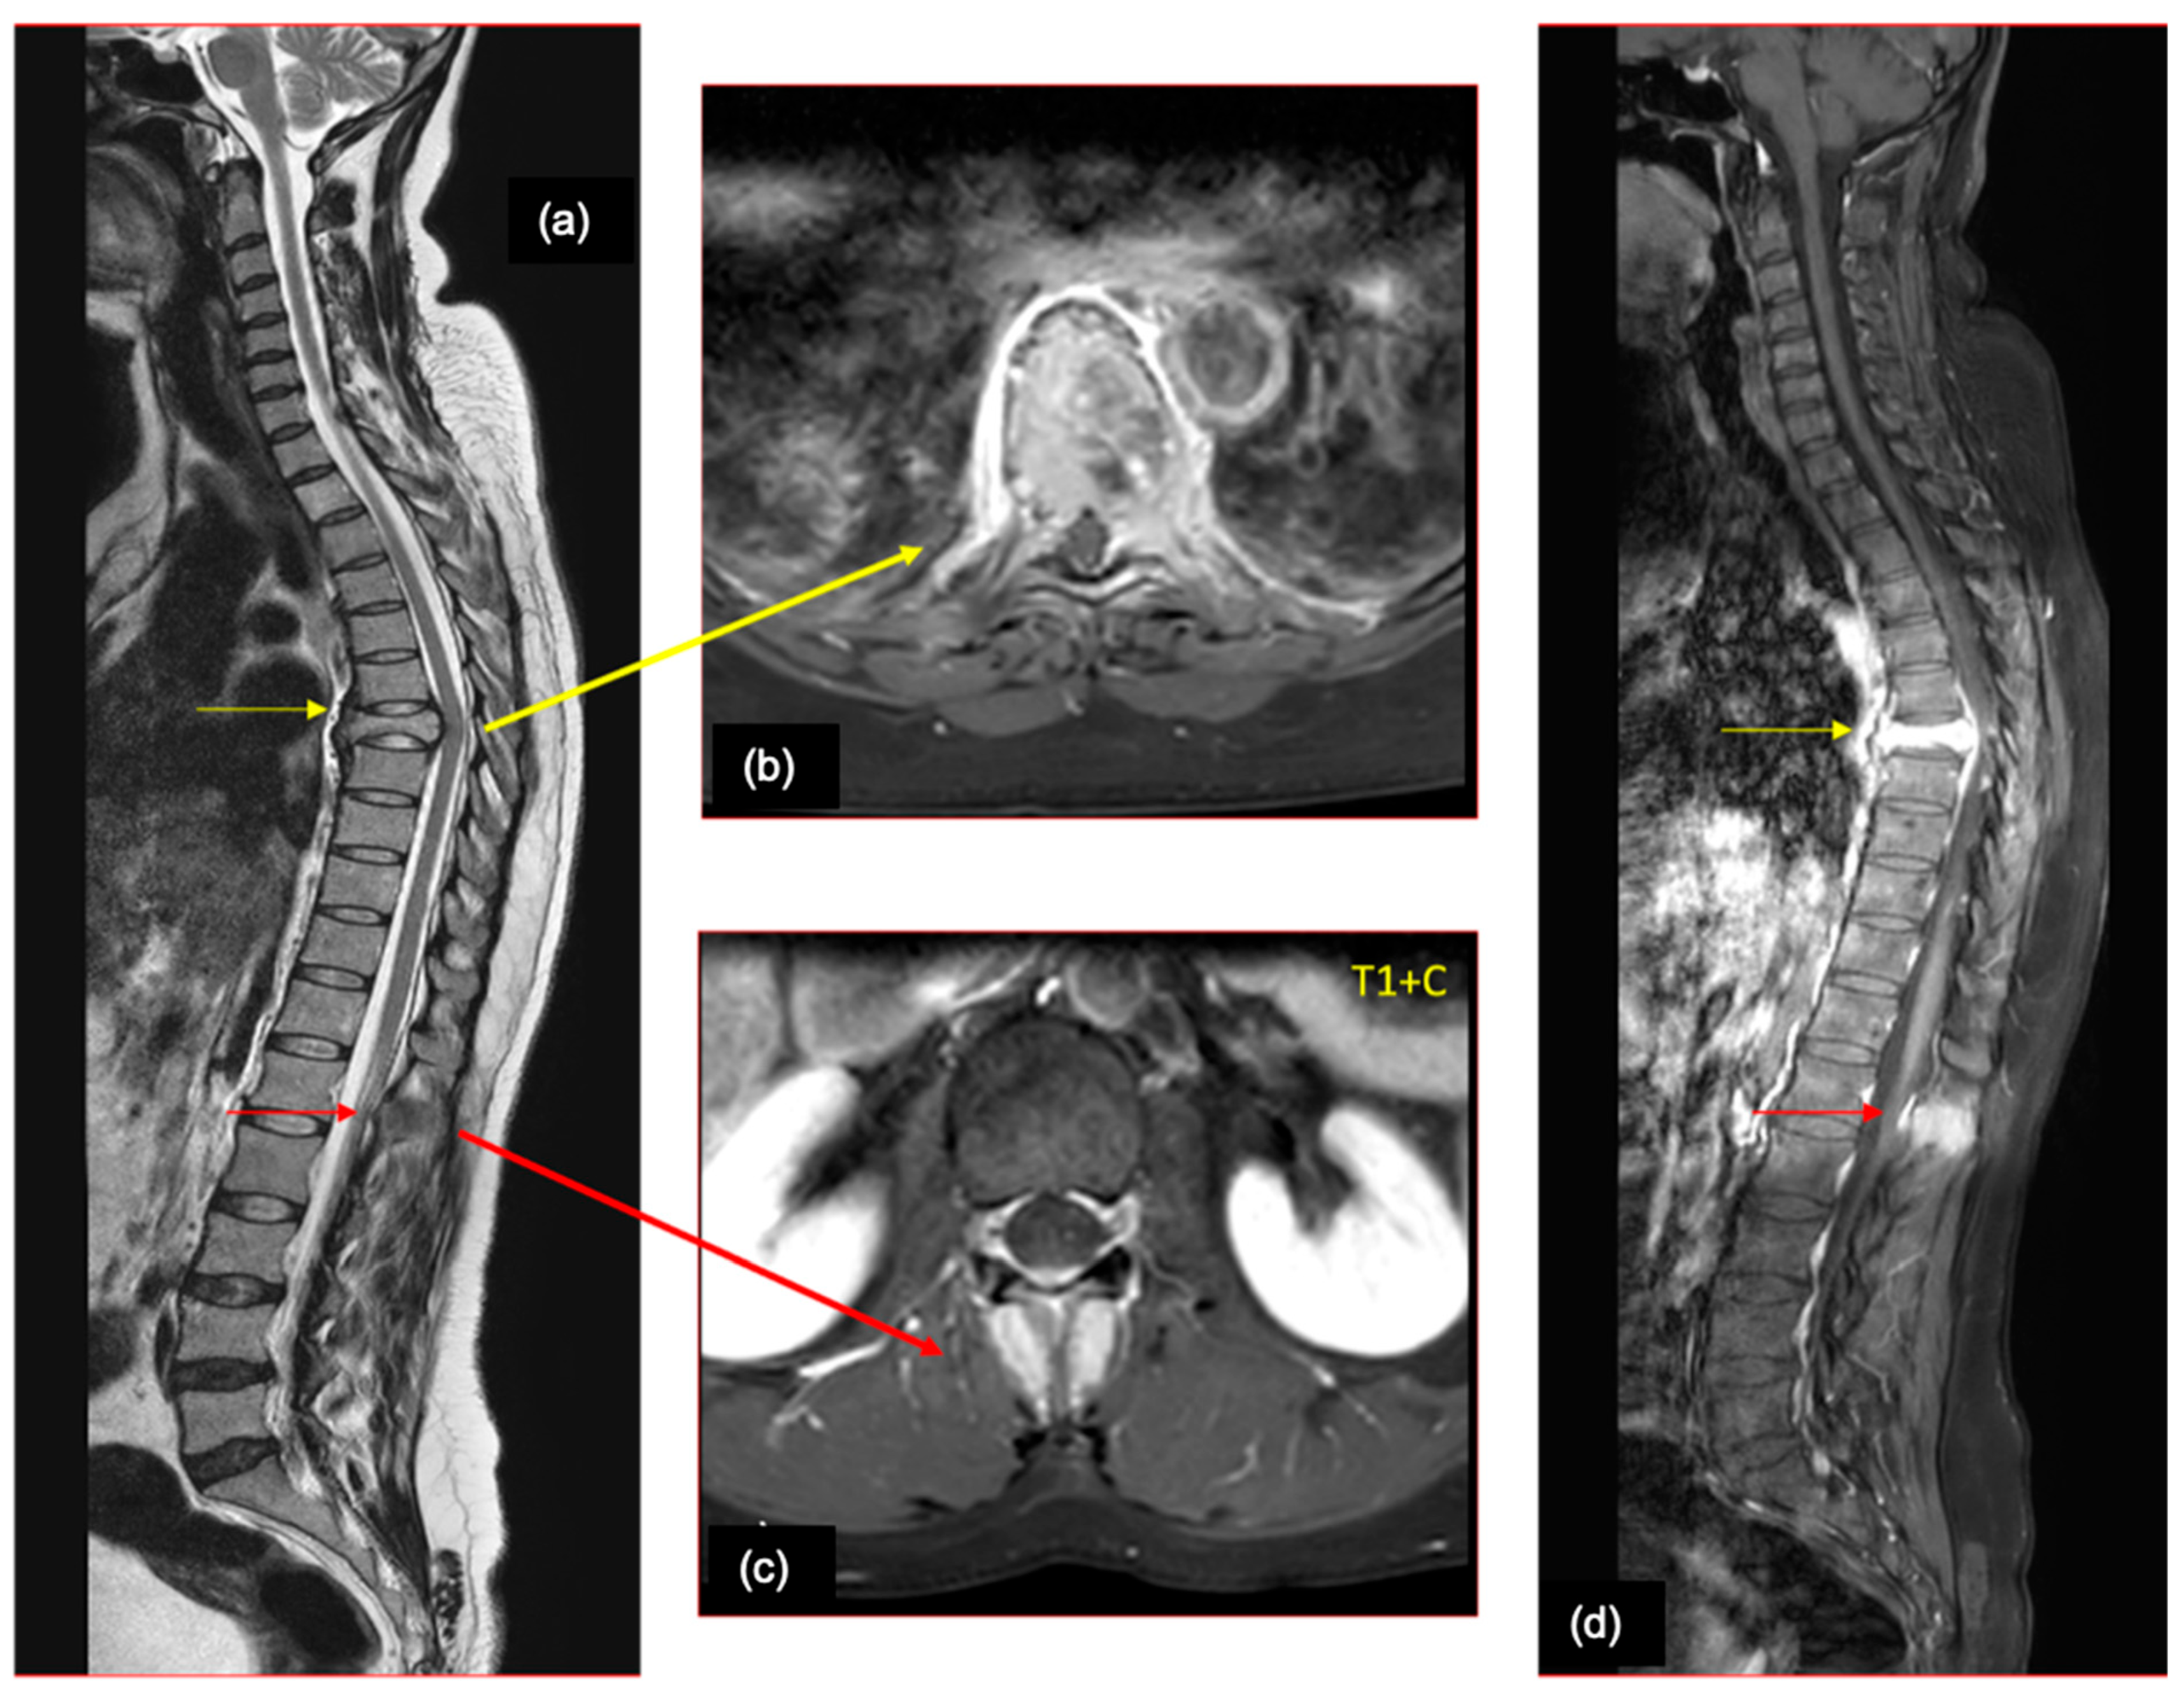

8. Spine Imaging

9. Etiopathogenesis

10. Presentation

11. Imaging Findings

12. Work-Up